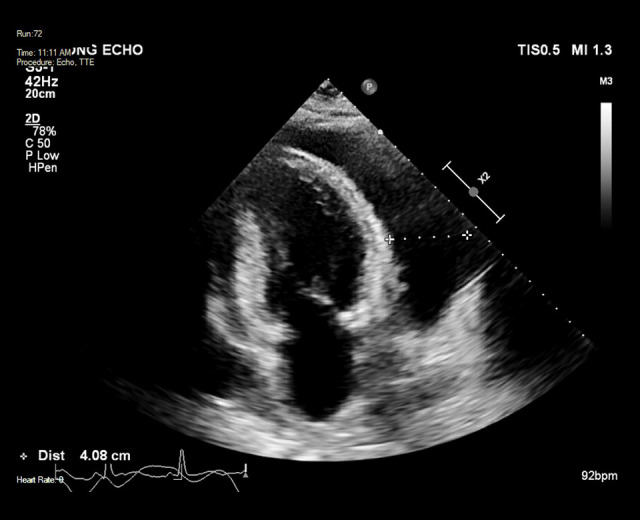

心包炎是系统性红斑狼疮(SLE)的常见并发症。然而,大量心包积液引起的心包填塞是一种罕见的后遗症。SLE患者发生心包填塞的危险因素包括女性、血清补体降低和诊断时抗核小体抗体阳性。心包填塞的治疗方案,如心包穿刺和心包开窗,都是针对个体量身定制的,并且缺乏关于何时进行侵入性干预的明确指南。病例报告:我们报告一例38岁女性SLE加重合并心包填塞,伴有发热、呼吸困难和胸膜炎性胸痛。胸片显示大量左侧胸腔积液掩盖了增宽的纵隔,怀疑为心包积液。在药物治疗试验后,患者出现了新的心房颤动、低血压和心动过速,并进行了心包穿刺,随后在接下来的24小时内抽出了1.6升心包液。采用高剂量脉冲皮质类固醇和环磷酰胺治疗,疾病得到控制,积液无复发。结论:这似乎是文献中描述的SLE患者心包引流量最大的一例。心包填塞可发生在SLE病程的任何阶段。大量胸腔积液可模仿心包积液的症状,使诊断具有挑战性。采用侵入性和药物治疗相结合的方法可以达到最终的治疗效果。心包填塞发生的危险因素应在SLE恶化的早期识别,以确保及时治疗并避免进一步的并发症。

BACKGROUND Pericarditis is a frequently encountered complication of systemic lupus erythematosus (SLE). However, cardiac tamponade resulting from massive pericardial effusion is a rare sequela. Risk factors for cardiac tamponade in SLE include female sex, reduced serum complement, and positive anti-nucleosome antibody at diagnosis. Management options for cardiac tamponade, such as pericardiocentesis and pericardial window, are tailored to the individual, and clear guidelines for when to proceed with invasive intervention are lacking. CASE REPORT We present a case of cardiac tamponade associated with an SLE exacerbation in a 38-year-old woman, associated with fever, dyspnea, and pleuritic chest pain. A chest radiograph demonstrated a large left pleural effusion obscuring a widened mediastinum suspicious for pericardial effusion. After a trial of medical therapy, the patient developed new atrial fibrillation, hypotension, and tachycardia, and proceeded to pericardiocentesis following which 1.6 liters of pericardial fluid was drained over the following 24 hours. Disease control was achieved with high-dose pulsed corticosteroids and cyclophosphamide and there was no recurrence of the effusion. CONCLUSIONS This appears to be one of the largest volumes of pericardial drainage described in the literature in the setting of SLE. Cardiac tamponade can occur at any stage of the disease course in SLE. Large pleural effusions can mimic symptoms of pericardial effusion and make diagnosis challenging. Definitive management can be achieved using a combination of invasive and medical therapy. Risk factors for the development of cardiac tamponade should be identified early in the course of an SLE exacerbation to ensure prompt treatment and avoid further complications.